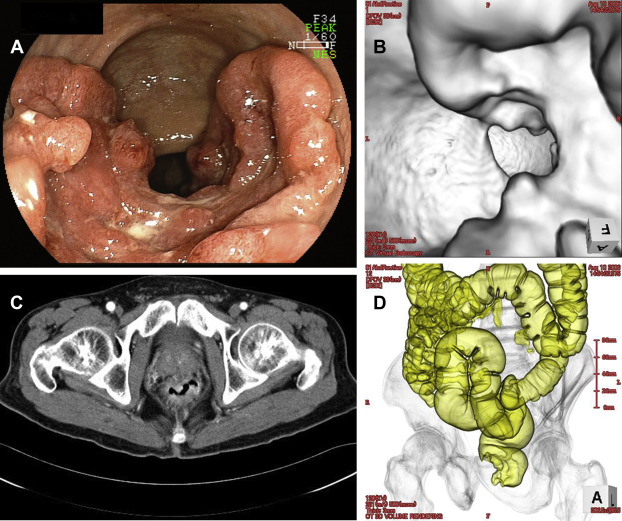

Images from a single patient with rectal cancer estimated by both colonoscopy and CTC (endoluminal image) to be 60% in circumferential extent are shown in Fig. 1. The median (interquartile range) circumferential tumor extent evaluated by colonoscopy for T1, T2, and T3/T4 were 10% (10–20), 30% (20–30), and 80% (20–100), respectively (Table 1). Circumferential tumor extent evaluated by colonoscopy for T1/T2 was significantly smaller than that for T3/T4 (p < 0.0001). The median (interquartile range) of circumferential extent evaluated by CTC (endoluminal image) for T1, T2, and T3/T4 were 10% (10–10), 30% (20–30), and 70% (20–100), respectively. Circumferential tumor extent evaluated by CTC for T1/T2 was significantly smaller than that for T3/T4 (p < 0.0001). The circumferential tumor extent could not be estimated by CTC for one patient in this study. In that particular patient, the tumor was T2, near the anal verge, and the insufflation was incomplete, but the circumferential tumor extent was estimated at 20% by colonoscopy. The correlation coefficient was very high (0.94) between the circumferential tumor extent evaluated by colonoscopy and CTC ( Table 2).

(A) Colonoscopy image of a tumor with 60% circumferential extent. (B) Computed ...

Figure 1.

(A) Colonoscopy image of a tumor with 60% circumferential extent. (B) Computed tomography (CT) colonography, endoluminal image of a tumor with 60% circumferential extent. (C) CT axial image of a tumor with 60% circumferential extent. (D) CT colonography, air enema image of a tumor with 60% circumferential extent.